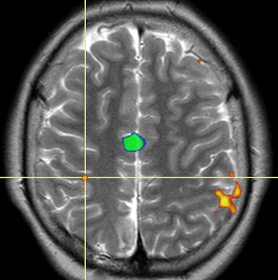

A frame image collection for your cases